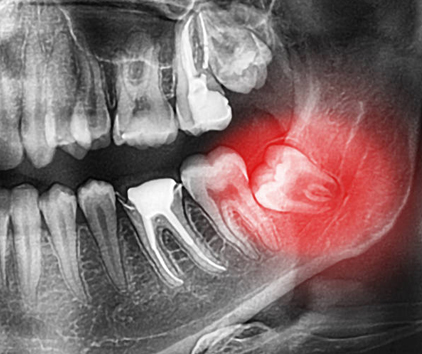

Dental X-rays, also called radiographs, are diagnostic images of your teeth, gums, and jawbones. They allow dentists to detect problems that are not visible during a visual examination, such as cavities, bone loss, infections, or impacted teeth.

• Panoramic X-rays: Capture the entire mouth, including teeth, jaws, and sinuses, to assess overall dental health and detect major issues.

• Assessing Hidden Issues: Reveals impacted teeth, abscesses, bone loss, and jaw problems that are not visible to the naked eye.

• To assess wisdom teeth or identify impacted teeth.